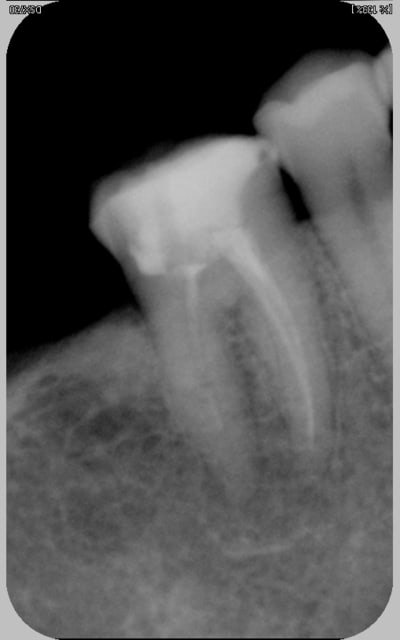

la roulette russe c'est savoir s'il y a une balle dans le chargeur? en gros comment poser l'indication du RTE?

là la dame avait une belle tumefaction ggale et la dent douloureuse a la pression. je fais une radio (comment faire autrement?)

la tumefaction est bien en regard du canal distal qui ne parait pas tip top, pourtant je doute encore car je sais que son prat endodontise bien d'habitude. La dent est restaurée avec un compo collé (mais j'ai pas de photo là, dommage, il était chouette)